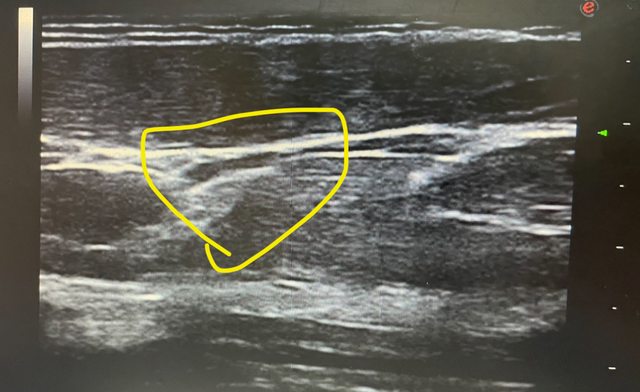

各位好 今天我陪家人去復健科照前臂部位的超音波 醫生看完報告後 說前臂外上髁肌肉拉傷、筋膜剝離 醫生指出超音波圖中有一個白影就是剝離的筋膜 並指出沒有治療方案,醫生也不願意多解釋,只說不能復健,只能等他自己好 想請問板上有人也受過一樣的傷嗎? 是否有較積極的治療方式 我自己在網上找資料也找不到筋膜剝離之類的資料 ——— 附上超音波圖 醫生說黃圈處筋膜跟肌肉分離 https://i.imgur.com/Zx1mcf6.jpg

juor2: 筋膜可能撕裂,但要實際再看看,有時那只是肌肉的一端 01/04 00:12

juor2: 也可能是其他的。如果筋膜有受傷也是可以注射治療的 01/04 00:12

juor2: 只是也要作功能評估才知道是不是這東西所造成 01/04 00:12

scotthsiung: 真正筋膜拉傷確實需要等... 不能一直拉扯 01/04 10:35

scotthsiung: 有一種說法是中醫的針灸很像刺激筋膜的反映位置 01/04 10:37